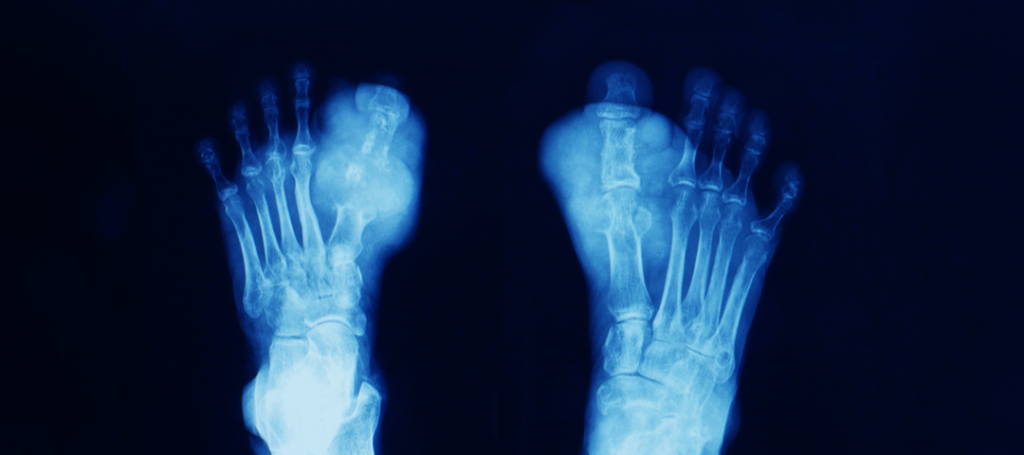

La gota es una enfermedad reumática que se da por una acumulación de cristales microscópicos de ácido úrico en las articulaciones.

La gota se manifiesta en ataques bruscos de dolor intenso en las articulaciones afectadas, así como hinchazón. Estos episodios suelen repetirse y en ocasiones, además de las articulaciones de pies, tobillos, rodillas o muñecas, pueden inflamarse las bolsas sinoviales y los tendones.

Si se deja evolucionar la enfermedad sin tratamiento, puede afectar a varias articulaciones, incapacitando de modo importante al paciente. Además, en fases avanzadas aparecen acumulaciones palpables como nódulos duros, denominados tofos.